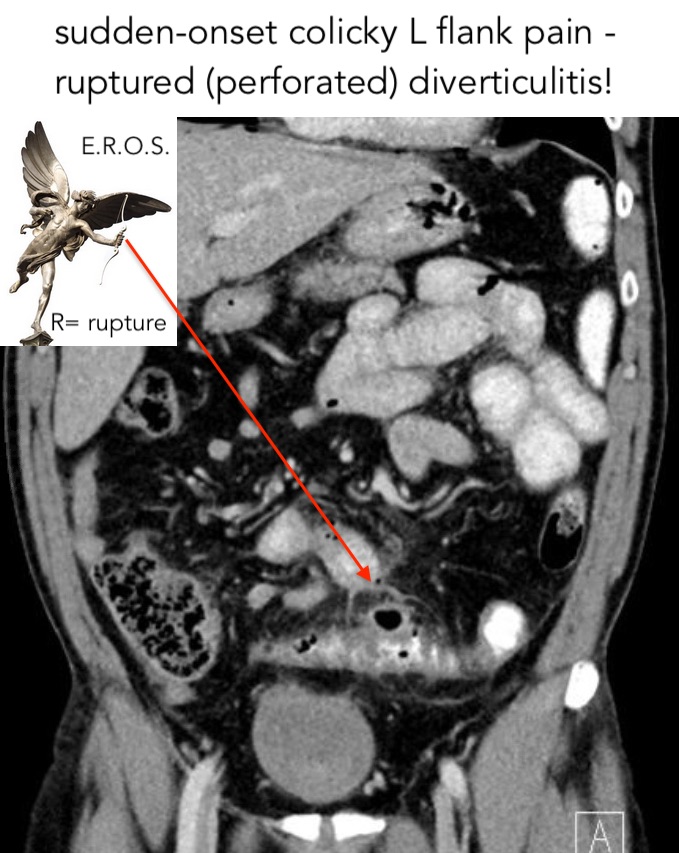

flank pain